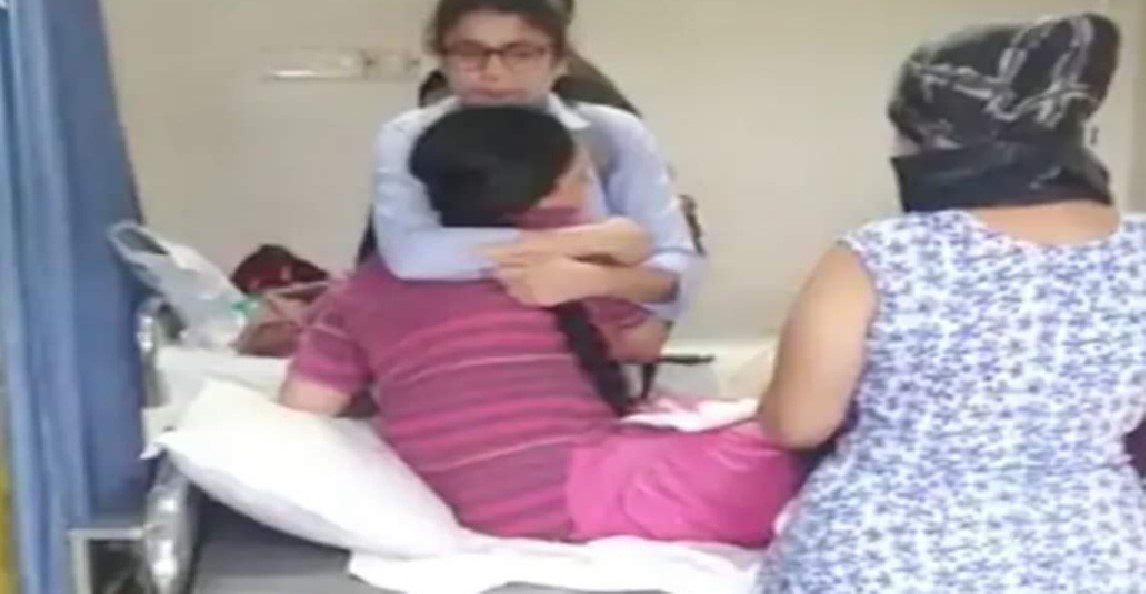

ડોક્ટરોએ બાળકના પેટમાંથી એક ચુંબક પણ બતાવ્યું અને કહ્યું કે બાળક અડધા કલાકમાં ચેતના પાછી મેળવી લેશે. પરંતુ લગભગ અઢી કલાક બાદ ડોક્ટરોએ જણાવ્યું કે બાળકનું મોત થયું છે. પરિવારે આરોપ લગાવ્યો કે બાળકનું મોત એનેસ્થેસિયાના ઓવરડોઝને કારણે થયું છે. પરિવાર માટે આ સમગ્ર ઘટના માટે હોસ્પિટલ મેનેજમેન્ટ અને ડો.સોનલ નિવસરકર જવાબદાર ગણાવ્યા છે.

તે જ સમયે, બાળકના મૃત્યુ પછી પરિવારના સભ્યોએ તરત જ પોલીસને બોલાવી હતી. જે બાદ પોલીસે હોસ્પિટલ આવીને આ મામલાની તપાસ કરી હતી. કહેવામાં આવી રહ્યું છે કે પરિવારના સભ્યોએ હોસ્પિટલ મેનેજમેન્ટ વિરુદ્ધ ચંદનનગર પોલીસ સ્ટેશનમાં ફરિયાદ કરી છે.